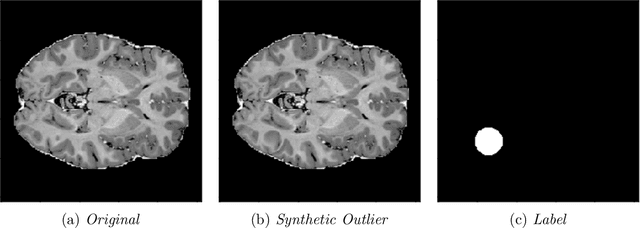

Abstract:In medical imaging, outliers can contain hypo/hyper-intensities, minor deformations, or completely altered anatomy. To detect these irregularities it is helpful to learn the features present in both normal and abnormal images. However this is difficult because of the wide range of possible abnormalities and also the number of ways that normal anatomy can vary naturally. As such, we leverage the natural variations in normal anatomy to create a range of synthetic abnormalities. Specifically, the same patch region is extracted from two independent samples and replaced with an interpolation between both patches. The interpolation factor, patch size, and patch location are randomly sampled from uniform distributions. A wide residual encoder decoder is trained to give a pixel-wise prediction of the patch and its interpolation factor. This encourages the network to learn what features to expect normally and to identify where foreign patterns have been introduced. The estimate of the interpolation factor lends itself nicely to the derivation of an outlier score. Meanwhile the pixel-wise output allows for pixel- and subject- level predictions using the same model.